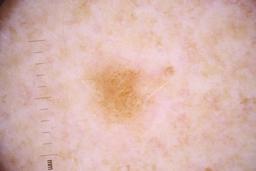

ISIC_4077341

- Challenge 2020: Training

- IP_1969685 IL_9238622

Clinical

| Field | Value |

|---|---|

| acquisition_day | 1 |

| age_approx | 50 |

| anatom_site_1 | Trunk |

| anatom_site_2 | Anterior trunk |

| concomitant_biopsy | False |

| dermoscopic_type | contact non-polarized |

| diagnosis_1 | Benign |

| diagnosis_confirm_type | serial imaging showing no change |

| family_hx_mm | False |

| image_type | dermoscopic |

| lesion_id | IL_9238622 |

| patient_id | IP_1969685 |

| personal_hx_mm | True |

| sex | male |